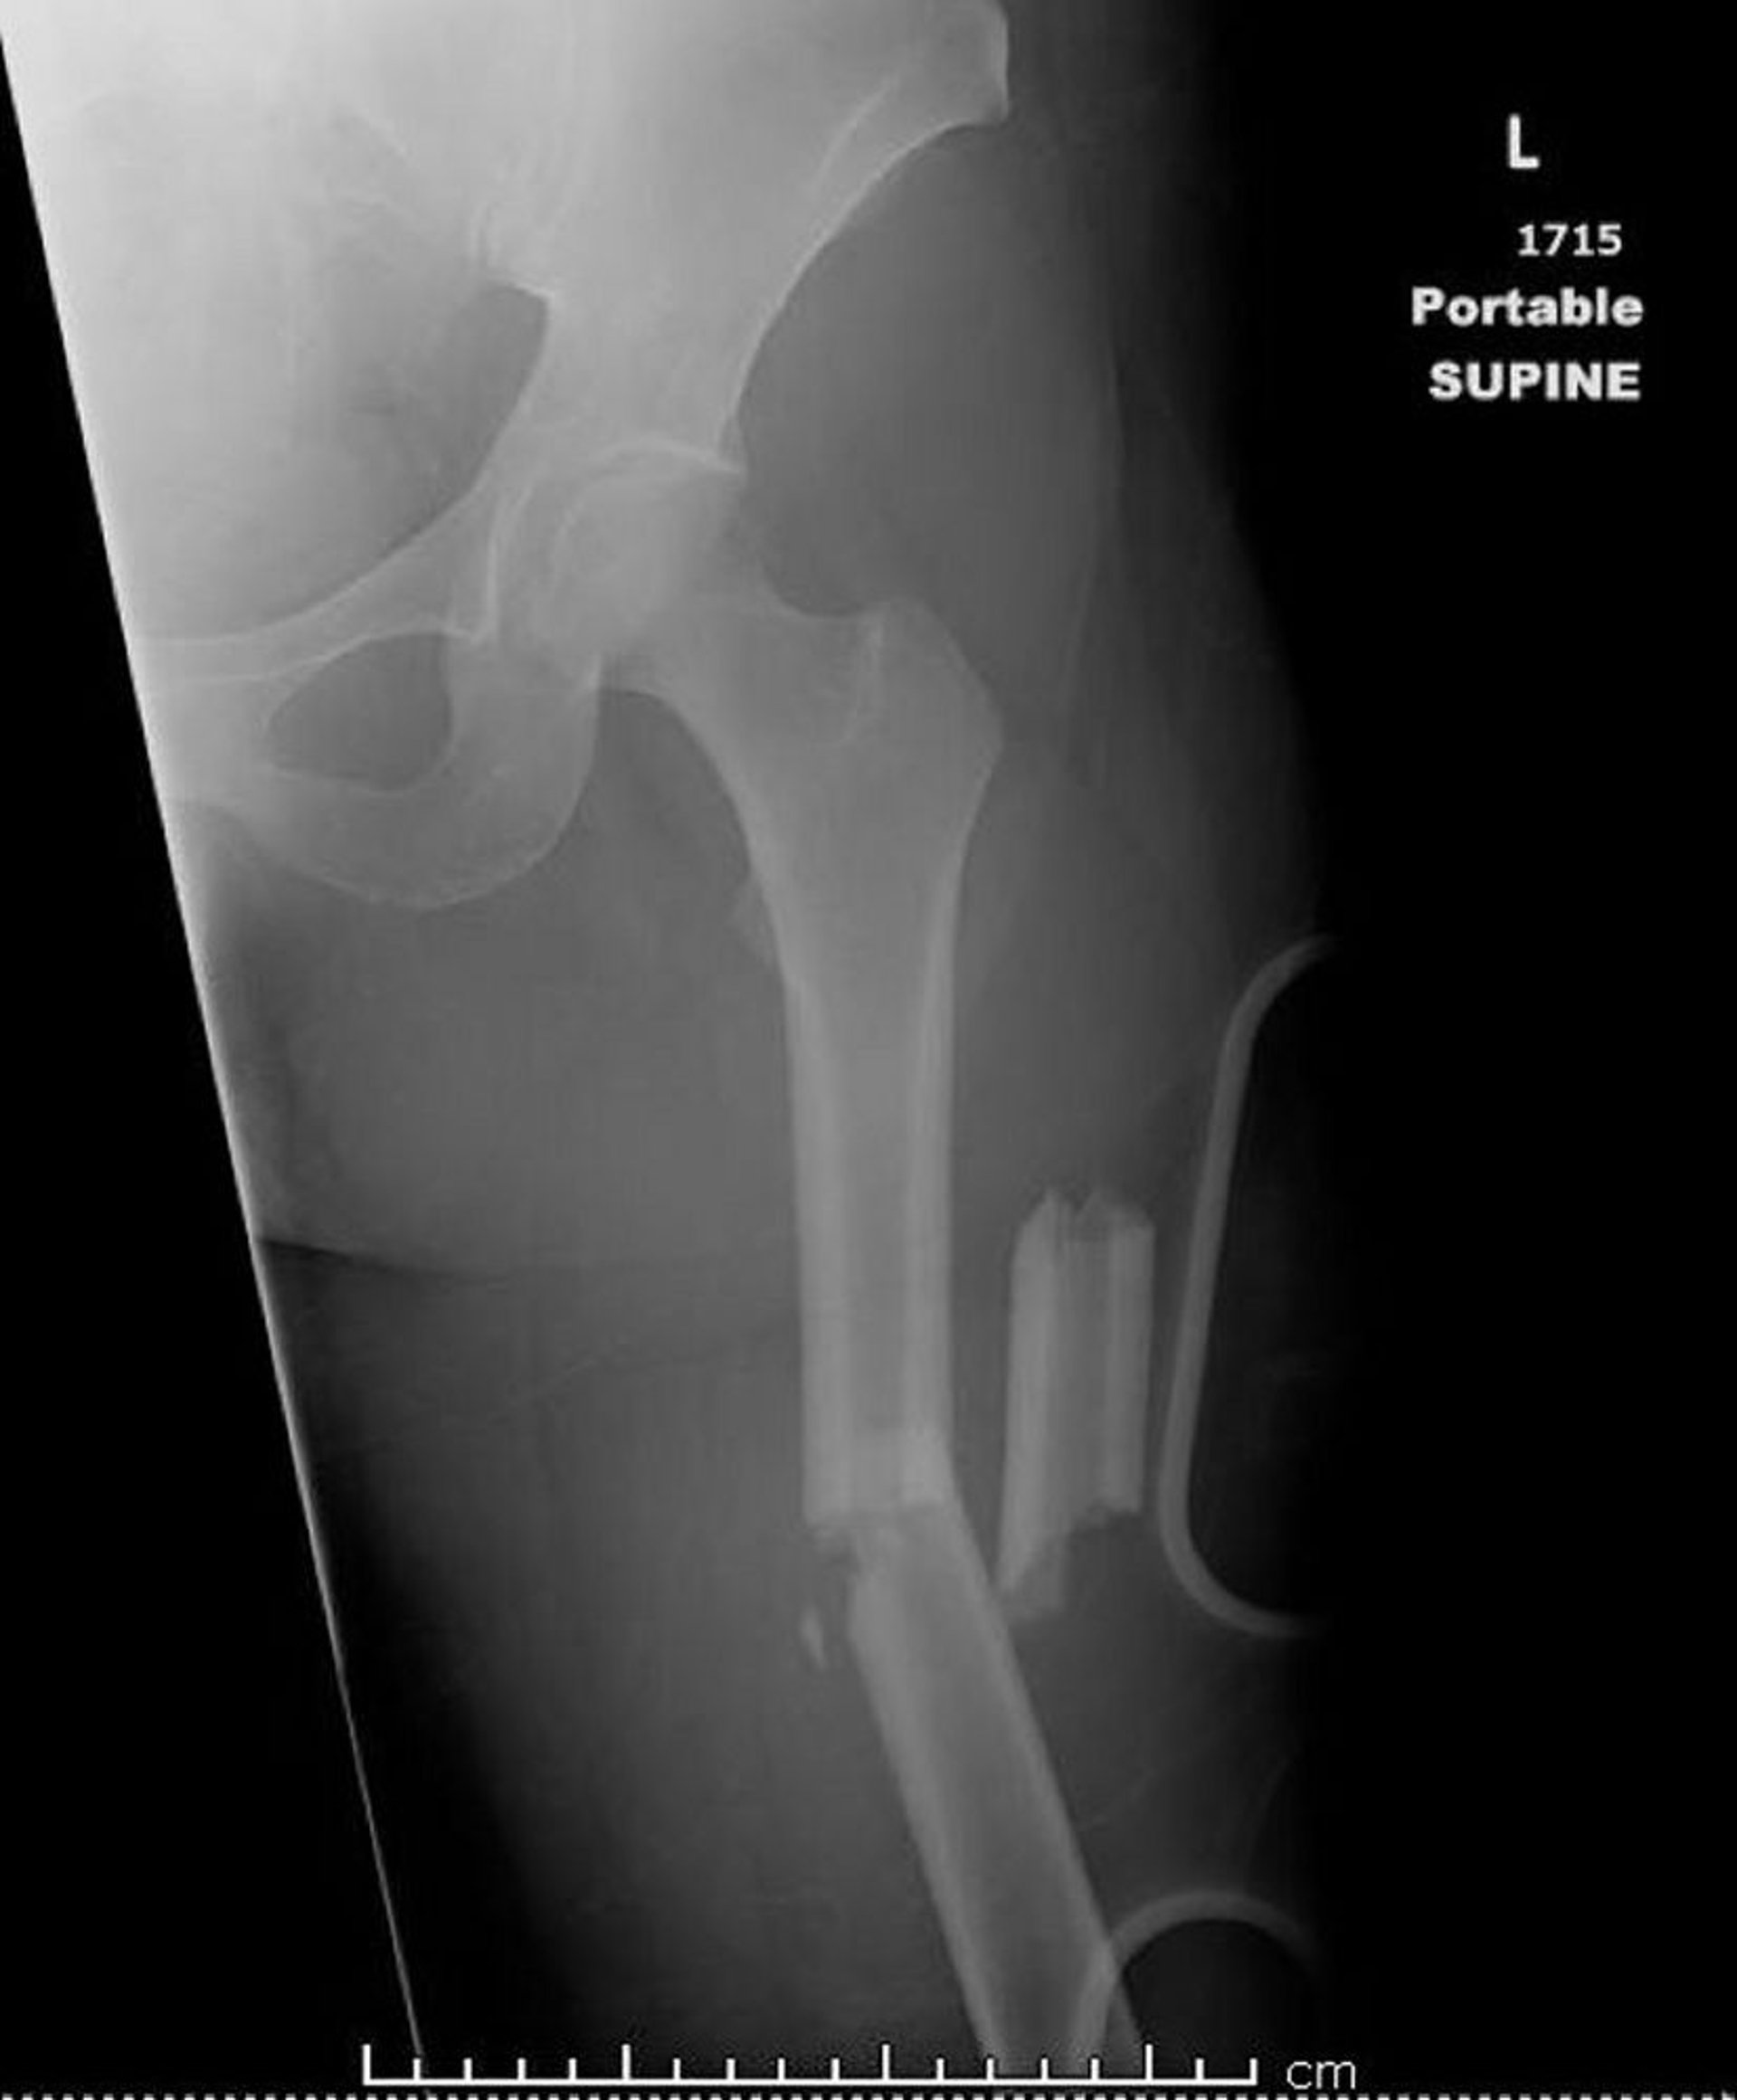

Перелом средней трети бедренной кости (1)

На этом изображении показан оскольчатый, угловой перелом средней части диафиза бедренной кости с укорочением.